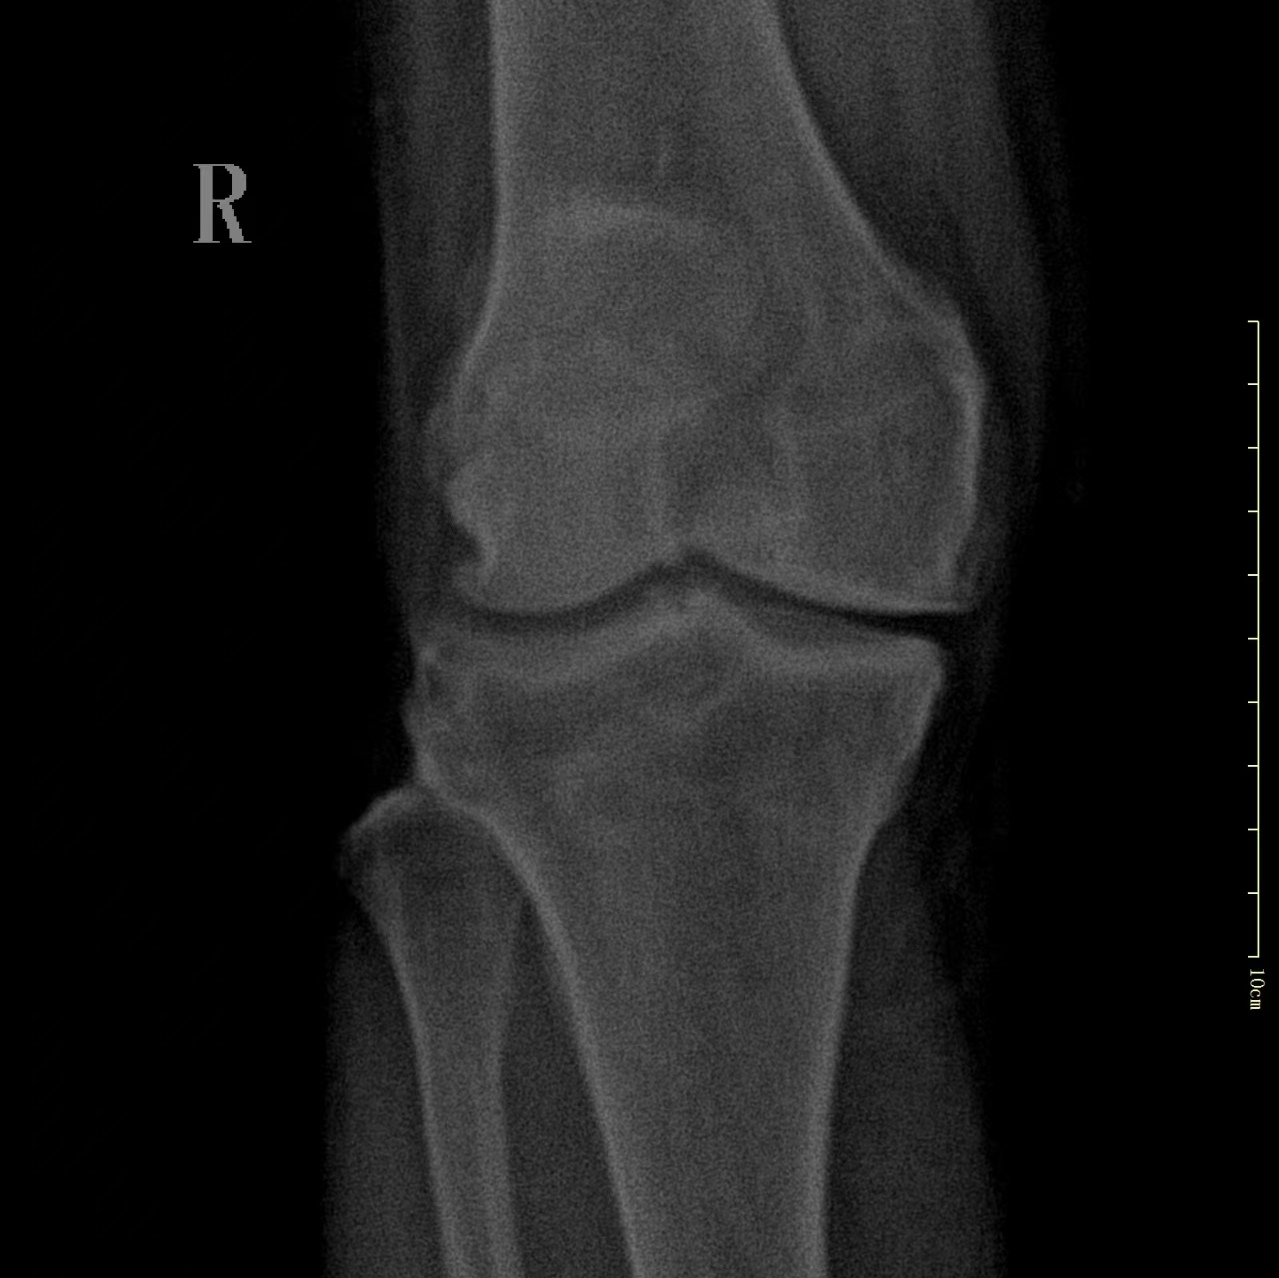

术 前